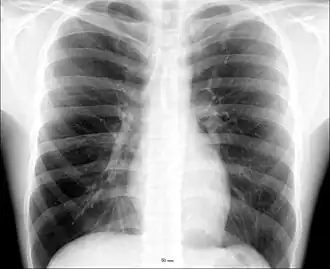

Thoraxfoto, het witte web rondom het hart bestaat uit de vaten uit de longhila | ||||

Het longhilum[2] (mv. hila) of hilum pulmonis[3] is de "opening" (hilum) in het longvlies, waar de bronchus en de slagaders en aders door het longvlies heen gaan. Een mens heeft twee longen, dus ook twee longhila. Een hilum bevat de longslagaders, de bovenste en onderste longader en een aftakking van de luchtwegen (met bloedvaten eromheen). In de hilumstreek (het mediastinum) liggen ook diverse lymfeklieren.

Op een thoraxfoto zijn de longhila altijd goed zichtbaar omdat de bloedvaten er zich sterk aftekenen tegen het omliggende longweefsel. Opgezwollen lymfeklieren rond de longhila (zoals bij sarcoïdose) zijn dan ook altijd goed te zien op thoraxfoto's.